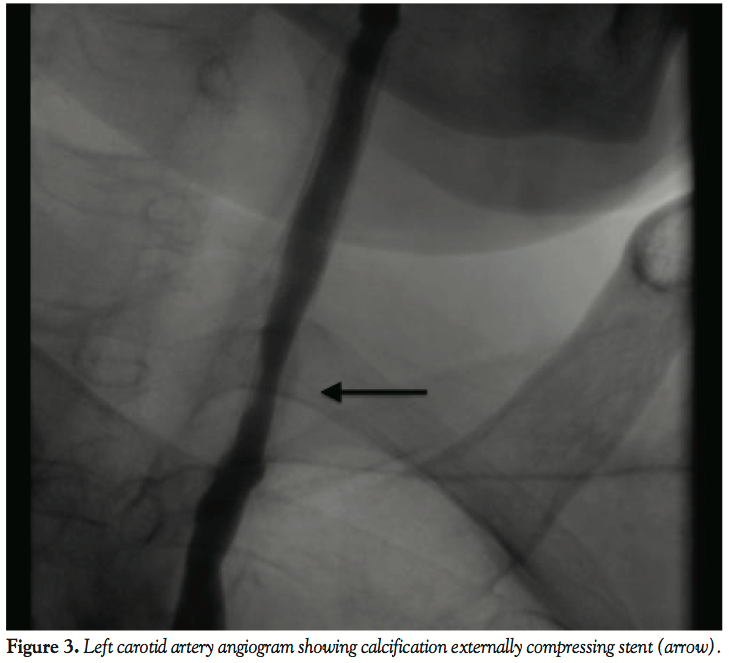

Six months later, the patient was diagnosed with significant restenosis at a different location within the original Xact stent (Figure 3). The ultrasound finding was confirmed with carotid angiography. This time, the stenosis was within proximal Xact stent apart from the Taxus stent, which showed no signs of restenosis. The stenosis was formed partly by neointimal hyperplasia, but mainly by surrounding calcification externally compressing the stent. Dilation of the stenotic segment with a 5.5 mm x 20 mm drug-eluting balloon (Elutax, Aachen Resonance) was done with a residual stenosis of less than 20%. Since then, the patient has been followed-up for another 30 months without any signs of increase of the flow velocities.